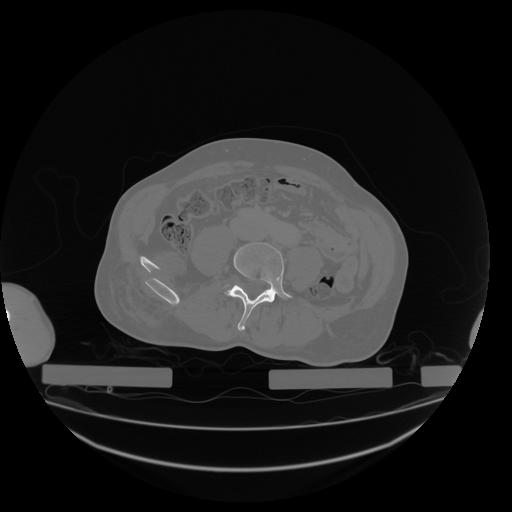

34 CUERPO,CE,Vol,1.0,CUERPO,,